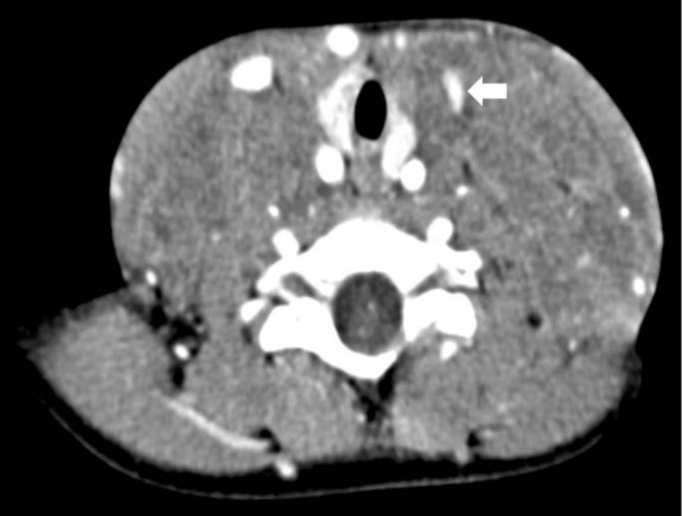

not invading them. Contrast-enhanced cervical CT scan revealed

a multicompartmental captive lesion involving the neck, with

extension to the upper and anterior mediastinum (Figure 2).

Figure 2:Axial image from a contrast-enhanced cervical CT scan

showing a multicompartmental, solid and captive lesion involving the

neck, with extension to the upper and anterior mediastinum and left

jugular vein compression. No evidence of calcification or compression

of the airway. There were no other cervical or mediastinal

adenopathies. View Figure